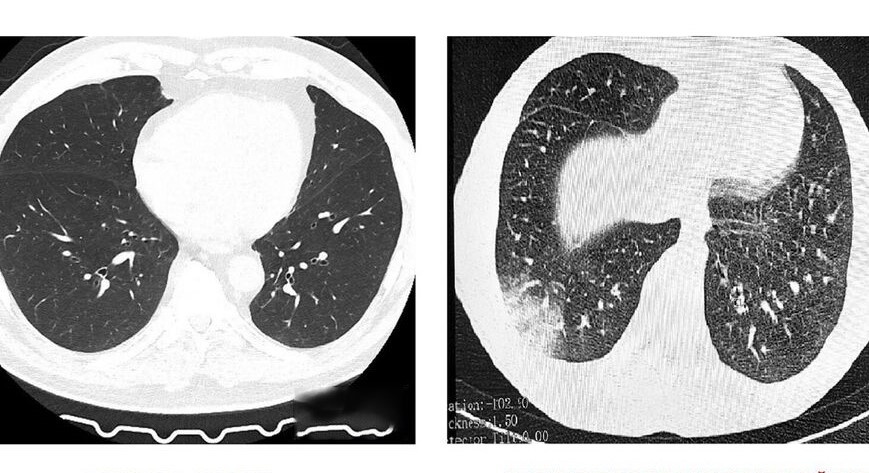

Честно говоря, да. Это воспаление и рубцевание самых мелких бронхов – бронхиол. Представьте себе тоненькие трубочки, по которым воздух поступает в легкие. Так вот, при облитерирующем бронхиолите эти трубочки сужаются, а иногда и вовсе зарастают. Воздуху становится трудно проходить, и человек начинает задыхаться.

А «попкорновыми легкими» эту болезнь прозвали из-за характерного звука, который слышен при прослушивании легких – он напоминает треск лопающегося попкорна. Жутковато, правда?